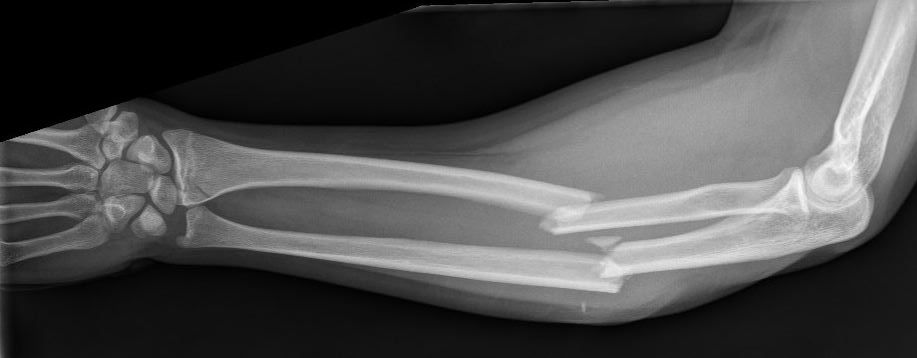

De breuk

Bij een breuk van de onderarm is er in principe sprake van een breuk van zowel het spaakbeen als de ellepijp. Omdat beide botten gebroken zijn, is er sprake van instabiliteit van de onderarm en zijn de breuken vaak verplaatst. Behalve een letsel van het bot is er ook vaak letsel van de zogeheten weke delen, zoals huid, pezen, spieren en eventueel vaten en zenuwen. Indien er sprake is van een ernstig letsel van de weke delen, kan dit leiden tot een open breuk (het bot komt dan in contact met buitenlucht) of zelfs uitval van de zenuwen en/of bloedvaten.